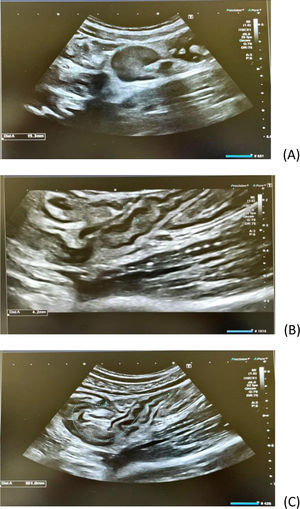

Tras dos meses de clínica, descartada patología local (vascular y traumatológica), se realiza ecografía abdominal (fig. 1). Se encuentra un engrosamiento patológico (4,2mm) de los últimos 10cm de íleon, con un grosor de la pared del colon derecho en el límite alto de la normalidad. Existen adenopatías patológicas en región ilecocecal; una de ellas alcanza los 15mm.

A la vista de los hallazgos ecográficos, se plantea la posibilidad de que estas adenopatías puedan ser la causa del edema por compresión de los vasos iliacos. En la anamnesis detallada, el joven niega síntomas generales, digestivos o dolor abdominal en los meses previos. Para completar el estudio etiológico, se sugiere hacer diagnóstico diferencial entre enterocolitis por gérmenes enteroinvasivos, tuberculosis y proceso linfoproliferativo.

Unos días después de realizar tratamiento con cotrimoxazol (trimetoprim/sulfametoxazol 160/800mg cada 12 horas durante siete días), se observa mejoría progresiva del edema. Se realiza una ecografía abdominal de control al mes, en la que se aprecia una normalización prácticamente completa de la adenopatía de mayor tamaño y una clara mejoría de la ileocolitis. El edema del MID remite completamente a los tres meses.